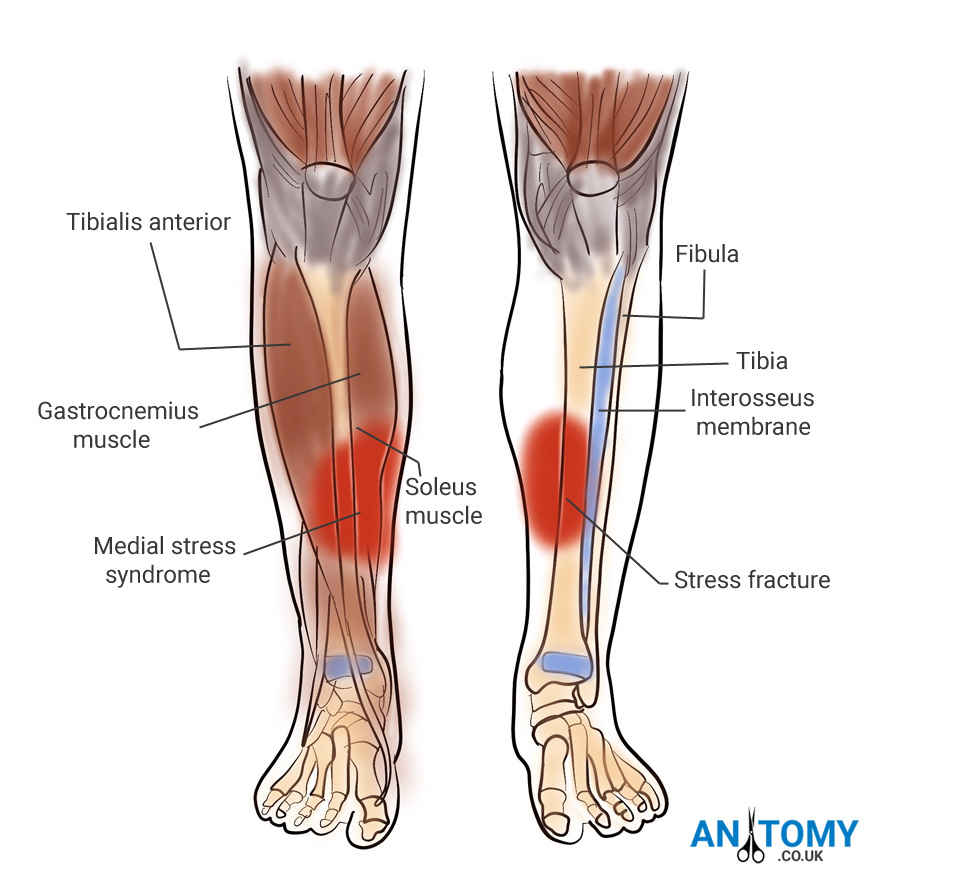

Анатомия фибулы: Подробные фотографии и схемы